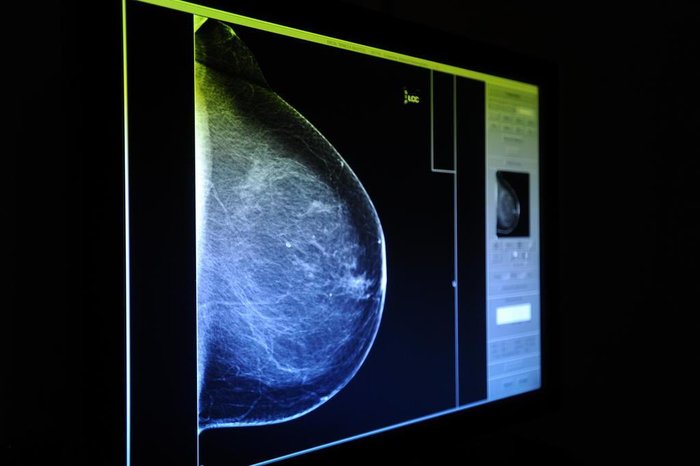

Um projeto de lei aprovado na Câmara de Vereadores de Porto Alegre prevê que todas as mulheres residentes em Porto Alegre possam realizar procedimentos como mamografia bilateral de rastreamento e ultrassonografia mamária por meio do Sistema Único de Saúde (SUS). A mudança na abrangência de acesso aos exames, hoje permitidos apenas para mulheres de mais de 50 anos, aguarda, agora, sanção do prefeito Sebastião Melo.

O projeto do vereador Jonas Reis (PT) prevê que a requisição para os exames dependerá da avaliação de profissional de saúde. Ainda, fica estabelecido que os exames deverão ser realizados em até 30 dias, contados da data da consulta em que foram solicitados. Também ficará garantida a realização de consulta de retorno para apresentação dos resultados.

Conforme o vereador Jonas Reis, era preciso fazer a regulamentação destes exames em Porto Alegre, permitindo que mulheres a partir dos 40 anos tenham acesso aos procedimentos. O parlamentar ressalta ainda que com esta mudança mais mulheres poderão fazer a prevenção, já que, atualmente apenas as que têm a partir dos 50 anos estão aptas ao procedimento.

GZH buscou médicos especialistas para entender a necessidade de estabelecer ou não um limite de idade para realizar uma mamografia bilateral de rastreamento e ultrassonografia mamária. Conforme a médica mastologista e chefe do núcleo da Mama do Hospital Moinhos de Vento, Maira Caleffi, determinar o acesso aos exames a partir dos 40 anos é a decisão mais acertada.

—Principalmente aqui em Porto Alegre, que é uma das cidades com o maior número de registros de câncer de mama do Brasil, os exames precisam ser anualmente e partir dos 40 anos. Isso não quer dizer que mulheres abaixo de 40 anos não tenham indicação para realizar os procedimentos, mas é preciso ter alguma queixa ou sintoma. Determinar a realização de mamografias a partir da puberdade, cientificamente, não tem nenhum valor —afirmou.